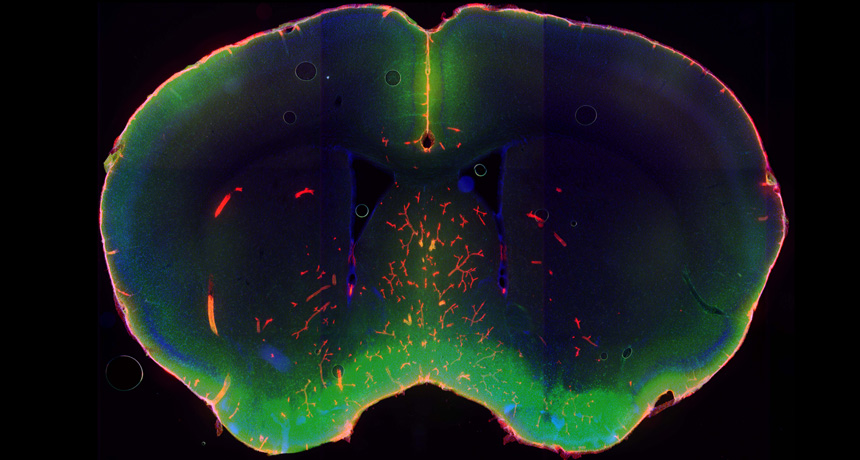

SLEEP CLEANER Tracer dyes (green, red) show where cerebrospinal fluid floods into the brain when a mouse is asleep. The fluid helps cleanse the brain of waste products that can build up and damage brain cells. Fluid flow nearly stops when the mice are awake.

L. Xie, H. Kang and M. Nedergaard